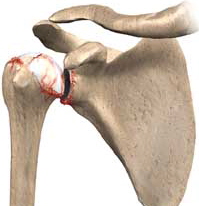

ΕΠΑΝΟΡΘΩΤΙΚΗ ΧΕΙΡΟΥΡΓΙΚΗ - ΩΜΟΣ